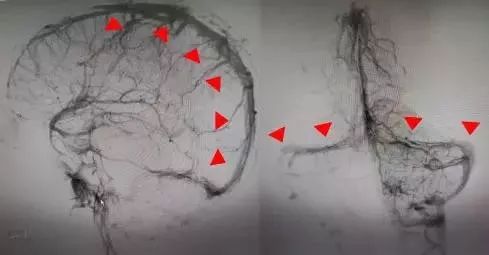

取栓前造影显示上矢状窦、双侧横窦及乙状窦充盈缺损、广泛血栓形成(红色箭头处)

术后造影显示上矢状窦、双侧横窦及乙状窦迅速开通(红色箭头处)